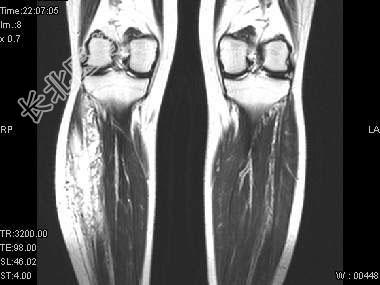

- 单项选择题男,15岁, 小时候发现左下肢肿胀,曾多次出血, 结合图像,最可能的诊断是 ( )

C、下肢血管瘤